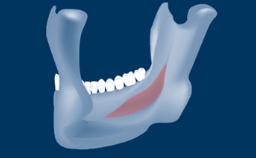

Digitally Guided Sinus Floor Elevation

In this short microlearning module on digitally guided sinus floor elevation, we delve into a specialized aspect of the digital workflow for implant-guided surgery, focusing on the use of digital guides in the sinus floor elevation technique.

- describe the indications for digital guides in SFE